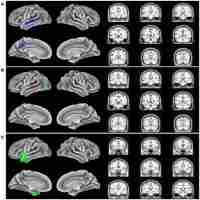

| Description | Journal: Alzheimer Disease & Associated Disorders The introduction of florbetapir (Amyvid) positron emission tomography biomarkers could dramatically change how we clinically evaluate young patients who present with nonamnestic cognitive complaints for possible Alzheimer disease (AD). Logopenic progressive aphasia (LPA) may be the most common example of this type of clinical problem. In most, but not all, cases, LPA is an early-onset AD variant presenting with language changes that can be difficult to distinguish from other progressive aphasias. We clinically evaluated 3 patients with LPA, in comparison with age-matched and severity-matched patients with typical amnestic AD, using florbetapir amyloid neuroimaging. The fluorodeoxyglucose-positron emission tomography scans of LPA patients revealed focal hypometabolism in the left temporoparietal areas, and the florbetapir scans were diffusely positive for the presence of amyloid deposition. The florbetapir scans did not differ in distribution between patients with LPA and those with typical amnestic AD. Clinical amyloid imaging, although lacking localizing value, is a major advance in the assessment of early-onset and nonamnestic patients for the presence of β-amyloid Alzheimer pathology. |